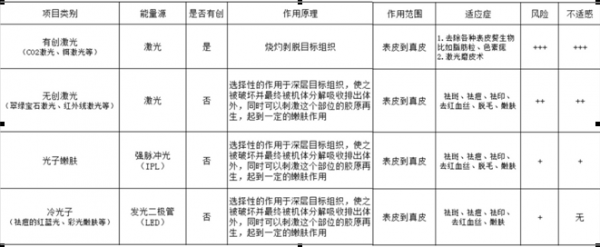

毕业之后自己工作了来到纽约,有更多的渠道去了解不同的讯息了。虽然我还是没有勇气去在脸上动真刀,但是我迈出了医美的第一步:激光和光子嫩肤。我去咨询了专业的医美医生,确认了我脸上沉积的色素是可以通过激光和强脉冲光消除的,于是二话不说的开始了我的疗程。当时住在新泽西找了一个在fort Lee的韩国医生,价格说实话也不便宜,让我一次交了5次的费用,一共是2500,也就是500一次。但是我后来转念一想,如果能快速有效的解决我的色斑问题,那这点钱花的也完全值啊。我买了那么多美白精华护肤品化妆品,加起来早就超过我现在做医美花的钱了。

毕业之后自己工作了来到纽约,有更多的渠道去了解不同的讯息了。虽然我还是没有勇气去在脸上动真刀,但是我迈出了医美的第一步:激光和光子嫩肤。我去咨询了专业的医美医生,确认了我脸上沉积的色素是可以通过激光和强脉冲光消除的,于是二话不说的开始了我的疗程。当时住在新泽西找了一个在fort Lee的韩国医生,价格说实话也不便宜,让我一次交了5次的费用,一共是2500,也就是500一次。但是我后来转念一想,如果能快速有效的解决我的色斑问题,那这点钱花的也完全值啊。我买了那么多美白精华护肤品化妆品,加起来早就超过我现在做医美花的钱了。 做完是不是超级光滑?虽然我不敢说无暇,但是我现在就完全从美妆爱好者变身素颜控!以前九点上课宁愿早上6点半7点起床,底妆修容高光眼影腮红眼线睫毛口红一个都不能落下,妆必须得完完整整了才出门。

美容医师建议,做完第一个疗程的治疗后(期间间隔一个月一次),建议半年至一年再做单独的一次巩固和消除一些因为日晒和辐射产生的一些新的色斑。

美容医师建议,做完第一个疗程的治疗后(期间间隔一个月一次),建议半年至一年再做单独的一次巩固和消除一些因为日晒和辐射产生的一些新的色斑。 因为IPL强脉冲光是无创的,感觉比之前做激光还要更舒服一些,对于我这种曾经做过激光的人来说,连麻药都不用敷。基本流程都和激光一模一样,只是IPL非常考验机器的设置和参数的调整。这家位于曼哈顿中城的Medical Spa使用的Viora是市面上最贵最先进有效的机器,比之前我随便找的Spa的国产IPL机器效果强100倍不说,也比我之前用的激光刺激小。其实除了纹身这样的色素沉积,好的机器的IPL都可以实现。

因为IPL强脉冲光是无创的,感觉比之前做激光还要更舒服一些,对于我这种曾经做过激光的人来说,连麻药都不用敷。基本流程都和激光一模一样,只是IPL非常考验机器的设置和参数的调整。这家位于曼哈顿中城的Medical Spa使用的Viora是市面上最贵最先进有效的机器,比之前我随便找的Spa的国产IPL机器效果强100倍不说,也比我之前用的激光刺激小。其实除了纹身这样的色素沉积,好的机器的IPL都可以实现。